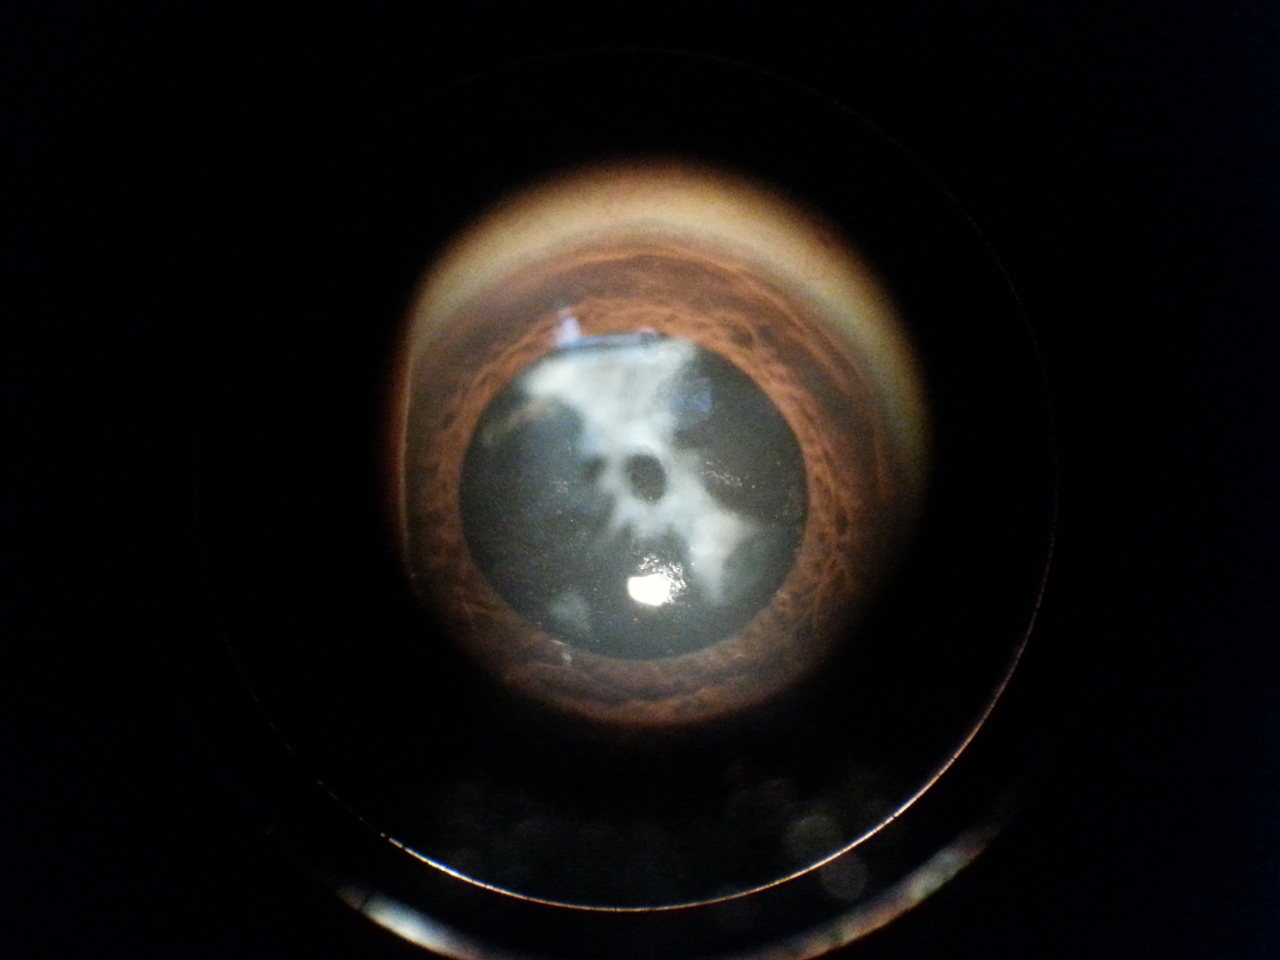

3 Fimosi e coartazione del sacco capsulare post intervento cataratta

Paziente di 44 anni ha effettuato un intervento di cataratta un anno fa, viene per una visita oculistica riferendo un forte abbassamento visivo nell'occhio operato.

L'obiettività oculistica è la seguente: visus, conta dita stentata; biomicroscopia, pseudofachia (presenza di cristallino artificiale post intervento di cataratta), fimosi e forte contrazione del sacco capsulare (vedi foto allegate); fundus, si esplora estremamente velato, non alterazioni evidenti.

Si programma intervento chirurgico di correzione di fimosi e contrazione del sacco capsulare.